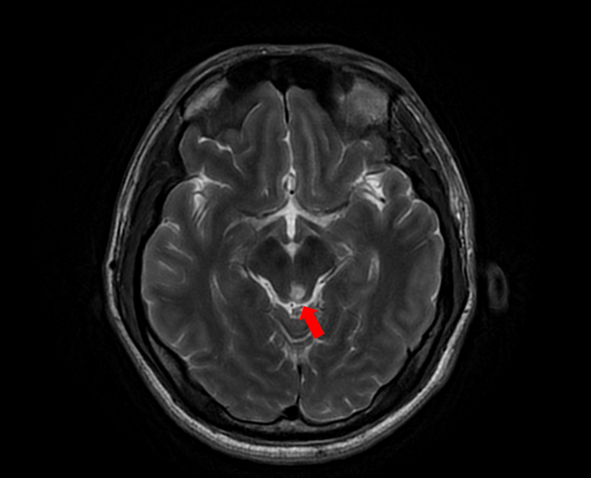

随着患者高先生颅内中脑左侧、左侧小脑两处病灶的顺利切除,国际神经外科医生集团专家已累计在苏大附四院完成了第100例高难手术。这标志着我院在神经外科国际化合作交流方面取得了里程碑式的成果,也为众多疑难脑肿瘤患者带来了新的希望。

自苏州大学附属第四医院与国际神经外科医生集团签约合作以来,Bertalanffy(巴特朗菲)教授、Froelich(福洛里希)教授等专家已多次来院开展深度医疗合作。在手术室里,国际专家与我院神经外科团队紧密配合,针对脑干、丘脑、颅底等高难度区域的复杂肿瘤,实施了包括脑干海绵状血管瘤、颅底脑膜瘤、复杂胶质瘤等一系列高风险手术。百例手术,不仅是数字的积累,更是技术与信任的双重见证。